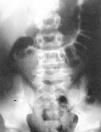

Casos clínicosCaso 1: varón de 11 años, con antecedentes de herniotomía inguinal izquierda, que ingresa por febrícula y dolor abdominal de 24 h de evolución, sin otra sintomatología acompañante. En el examen físico presenta distensión abdominal con timpanismo generalizado y dolor localizado en la fosa iliaca derecha (FID), con signos de irritación peritoneal. En las pruebas complementarias presenta leucocitosis con neutrofilia y en la radiografía simple de abdomen (fig. 1) se observa calcificación aislada en la FID indicativa de coprolito. Ante la sospecha de abdomen agudo quirúrgico, se practica una laparotomía con hallazgo intraoperatorio de una tumoración cecal, de consistencia firme, que engloba el apéndice, el cual se encuentra engrosado y retraído, con coprolito impactado en su interior. Se intenta realizar una reducción manual de la invaginación apendicocecal sin éxito, por lo tanto, se reseca la tumoración incluyendo la base periapendicular, seguida de plastia cecal y biopsia ganglionar mesentérica. El estudio histológico confirma la invaginación del apéndice (fig. 2), con apendicitis aguda secundaria a coprolito calcificado y ganglio mesentérico con hiperplasia linfoide reactiva.